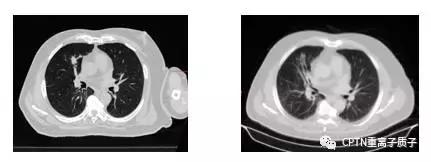

早期(心脏右旁约1*2cm的肿瘤)非小细胞肺癌患者,70岁高龄,为接受过肠癌和肝转移2次手术后发生的第二个原发肿瘤。因肥胖和血氧饱和度低无法耐受肺癌手术,接受根治性质子放疗(10次),治疗过程中使用主动呼吸控制技术(ABC),保证肿瘤在治疗过程中位置稳定。放疗后半年肿瘤就几乎完全消失,CT上局部残留的阴影在PET/CT没有摄取,证实肿瘤完全消失,目前已经无瘤生存超过2年。治疗过程中和治疗结束后患者未有任何明显不良反应。